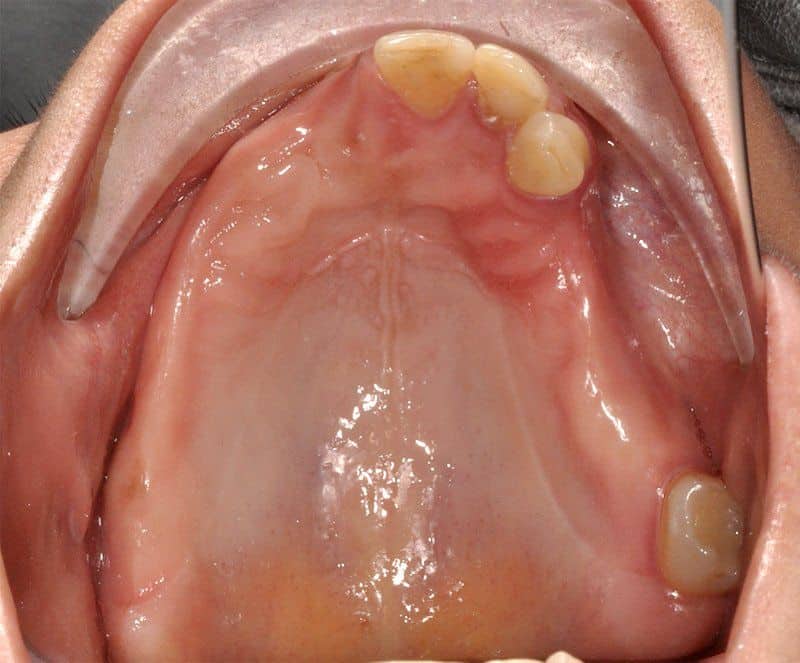

Los Implantes de Carga Inmediata son una solución práctica y definitiva para el desdentado total, es un tratamiento el cual una vez que se opera y se colocan los implantes, por un periodo entre 24 horas a 48 horas, se colocan los dientes en forma provisional, de esta forma el paciente queda con algo fijo mientras el implante se adhiere al hueso. Su principal ventaja radica en la reducción o eliminación del tiempo de espera entre la colocación del implante dental y la colocación de los dientes fijos.

Porque se hace en pabellones certificados por la Universidad de Chile. Son dependencias hechas única y exclusivamente para hacer intervención en sitios estériles. También se hace más cómodo y se pasa rápido el periodo de espera. Del momento en que se insertan los implantes debe transcurrir un período de tiempo de entre 4 a 6 meses si es en mandíbula o maxilar superiores respectivamente para que el tejido óseo cicatrice y logre integrarse a la superficie del implante